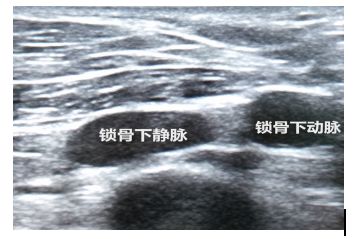

(二) 锁骨下静脉穿刺置管

超声引导锁骨下深静脉穿刺置管临床使用较少。具体方法参照传统经验性穿刺置管方法。

常规消毒铺巾、准备超声探头,使其平坦面接触皮肤,利用探头横向或纵向扫查血管走向,找到血管横截面(图7)或纵切面(图8),清楚探查到锁骨下静脉和动脉。仍需保证探头与穿刺针在同一平面,穿刺针在超声视野范围内。针尖进入血管后,回抽注射器,回血顺畅,穿刺针斜口完全位于锁骨下静脉,进一步常规置管固定。

图7 锁骨下静脉超声横截面二维图像

图8 锁骨下静脉超声纵切面二维图像